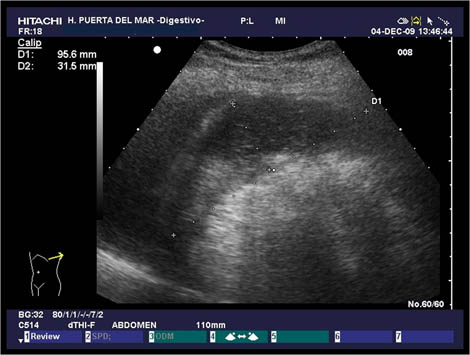

1.1. Cavidad peritoneal